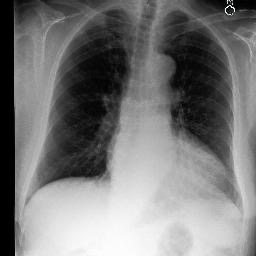

To address these issues, we propose a novel Adaptive patch-word Matching (AdaMatch) model to correlate chest X-ray (CXR) image regions with words in medical reports and apply it to CXR-report generation to provide explainability for the generation process. AdaMatch exploits the fine-grained relation between adaptive patches and words to provide explanations of specific image regions with corresponding words. To capture the abnormal regions of varying sizes and positions, we introduce the Adaptive Patch extraction (AdaPatch) module to acquire the adaptive patches for these regions adaptively. In order to provide explicit explainability for CXR-report generation task, we propose an AdaMatch-based bidirectional large language model for Cyclic CXR-report generation (AdaMatch-Cyclic). It employs the AdaMatch to obtain the keywords for CXR images and `keypatches' for medical reports as hints to guide CXR-report generation. Extensive experiments on two publicly available CXR datasets prove the effectiveness of our method and its superior performance to existing methods.